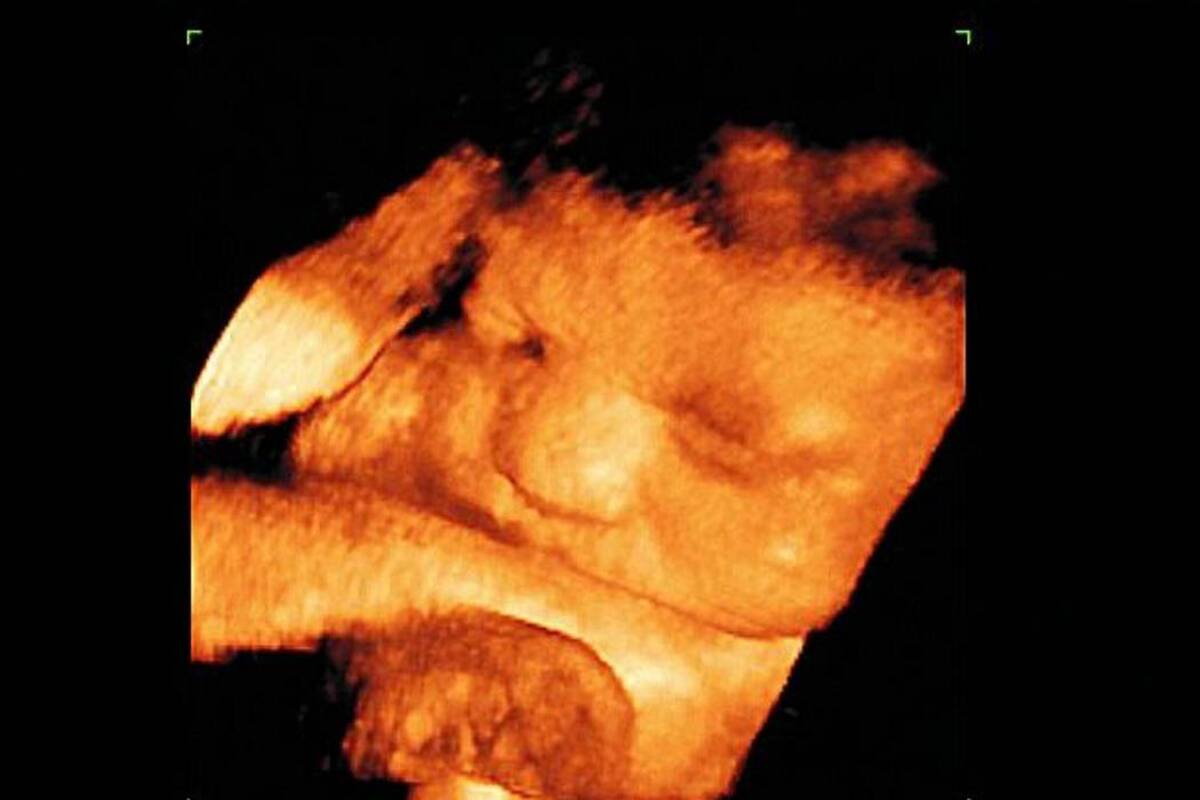

Se ha encontrado que la probabilidad de defectos congénitos es mayor en una mujer que tiene diabetes gestacional a una que no padece la enfermedad.

También otros problemas que pueden desarrollarse se relacionan con el peso, pueden haber recién nacidos con peso mayor o con problemas de bajo peso. El cuidado en el embarazo es un momento clave para la mujer y la vida de ese ser que está empezando a formar.